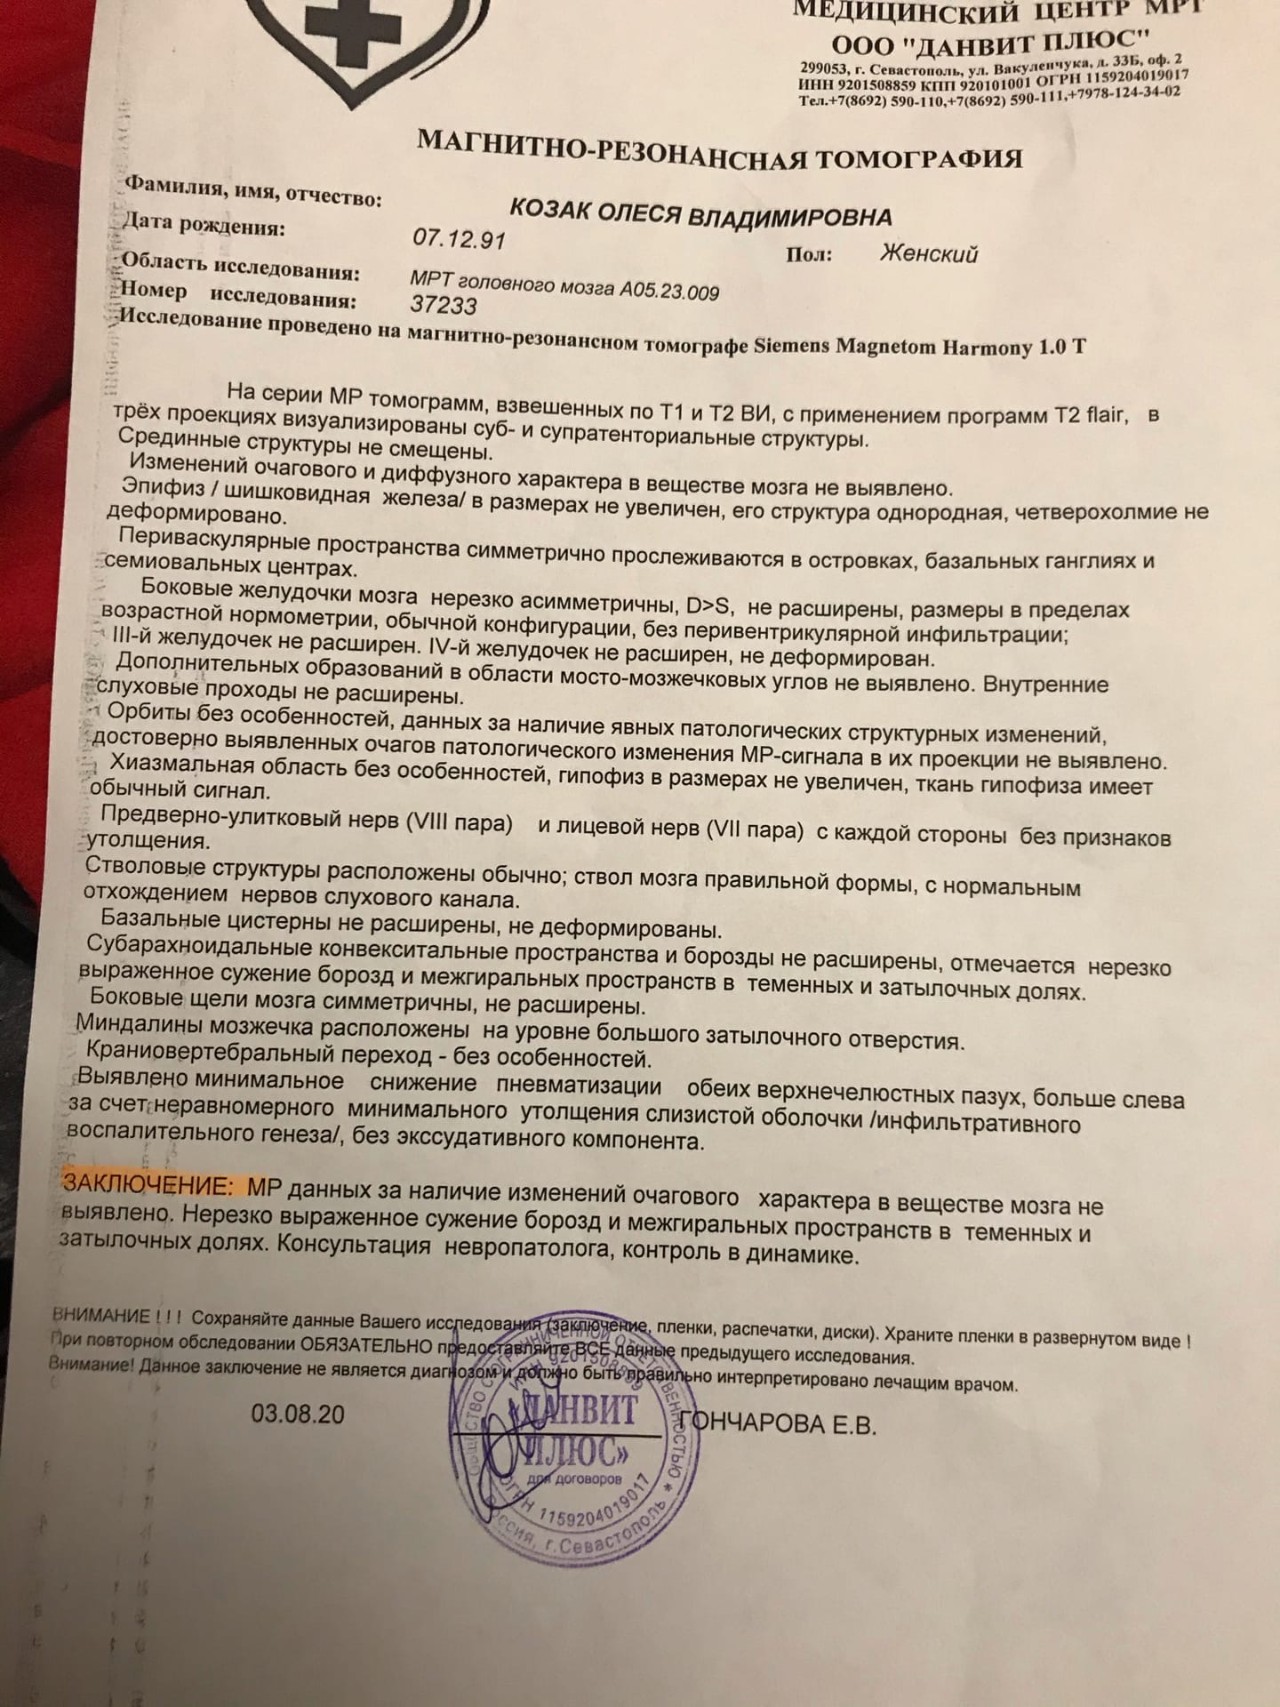

МРТ головного мозга: Расшифровка снимков и Интерпретация

Раздел: Визуальные уроки